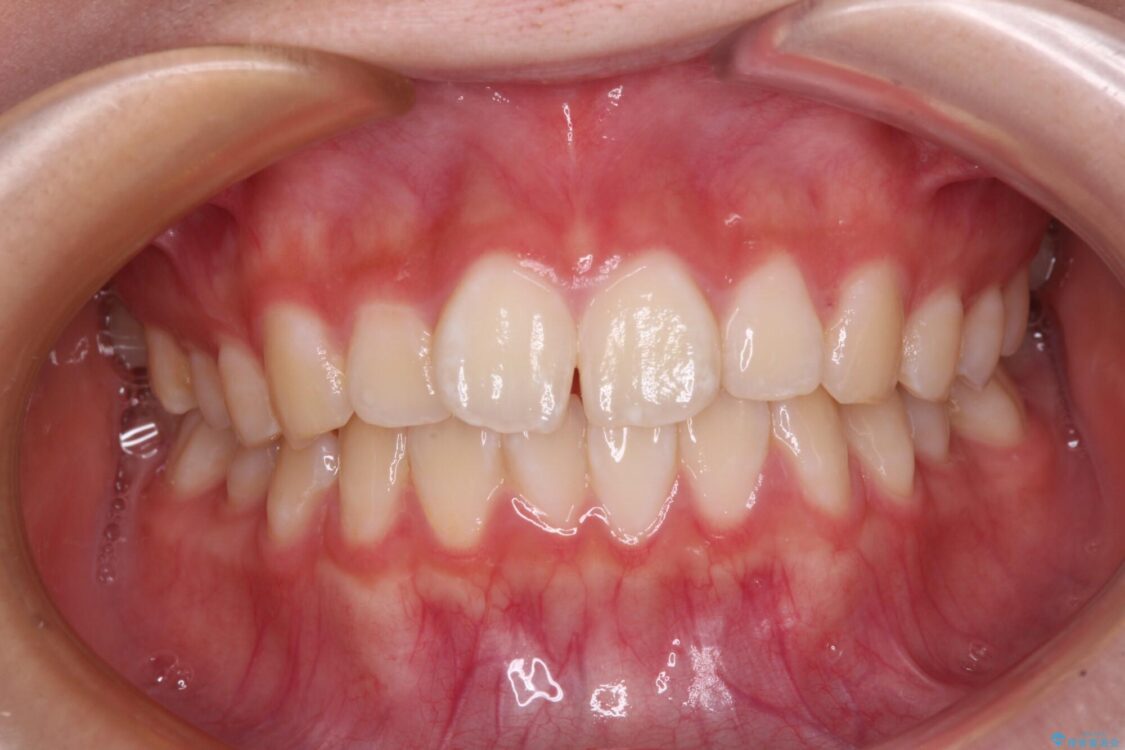

上下前歯のねじれを気にして来院された患者様です。

治療後

• インビザラインは使える自信がない ワイヤー装置にて矯正治療 治療後画像